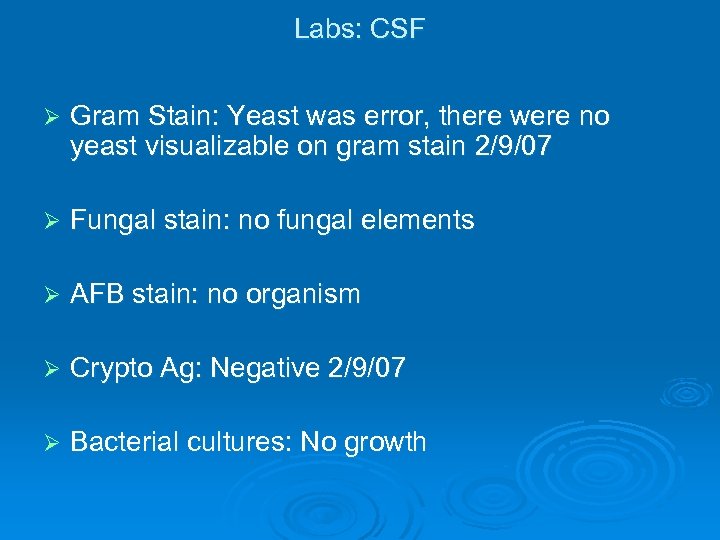

Labs: CSF Ø Gram Stain: Yeast was error, there were no yeast visualizable on gram stain 2/9/07 Ø Fungal stain: no fungal elements Ø AFB stain: no organism Ø Crypto Ag: Negative 2/9/07 Ø Bacterial cultures: No growth